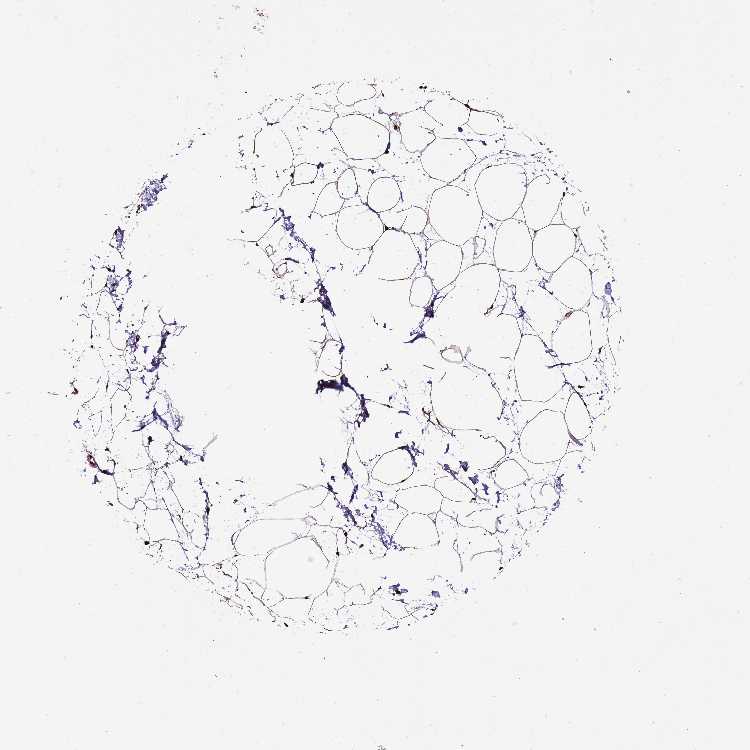

SOFT TISSUE 1 - Antibody stainingi

Antibody staining in the annotated cell types in the current human tissue is reported as not detected, low, medium, or high, based on conventional immunohistochemistry profiling in selected tissues. This score is based on the combination of the staining intensity and fraction of stained cells.

Each image is clickable and will lead to virtual microscopy that enables deeper exploration of all samples and also displays staining intensity scores, fraction scores and subcellular localization as well as patient and tissue information for each sample.

Antibody HPA046688

Chondrocytes High

Fibroblasts High

Peripheral nerve High